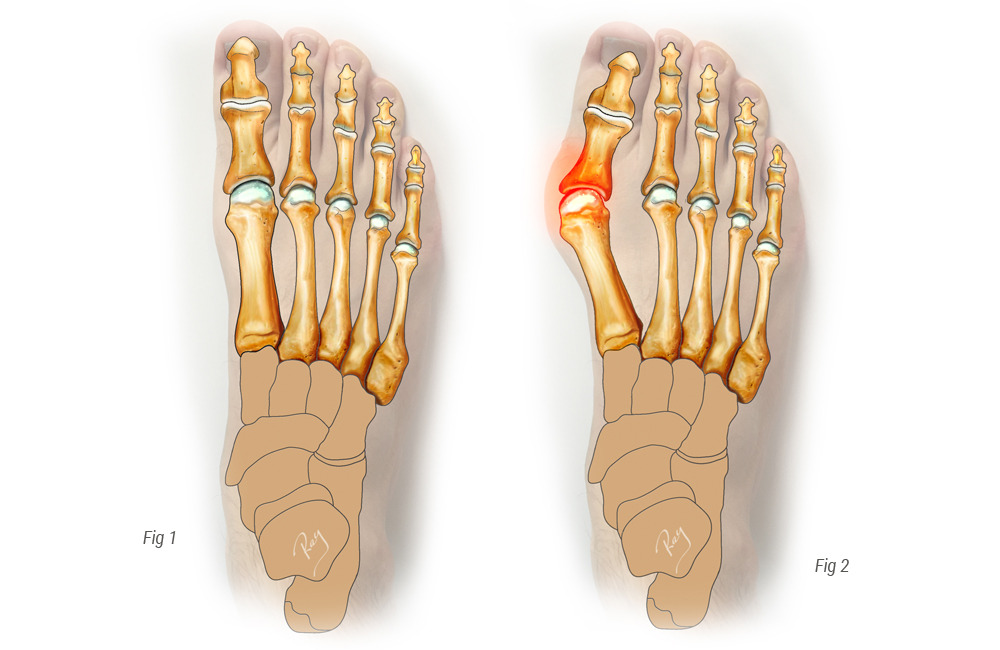

3. 무지외반증 (Hallux Valgus)

- 원인: 엄지발가락이 바깥쪽으로 휘면서 관절 부위에 지속적인 압력이 가해짐.

- 특징: 엄지발가락 관절 부위 돌출, 발바닥 앞쪽 압통.

- 위험 요인: 하이힐, 좁은 앞코 구두, 유전적 요인.

- 대처법: 편한 신발 착용, 발가락 교정기 사용, 심하면 수술.